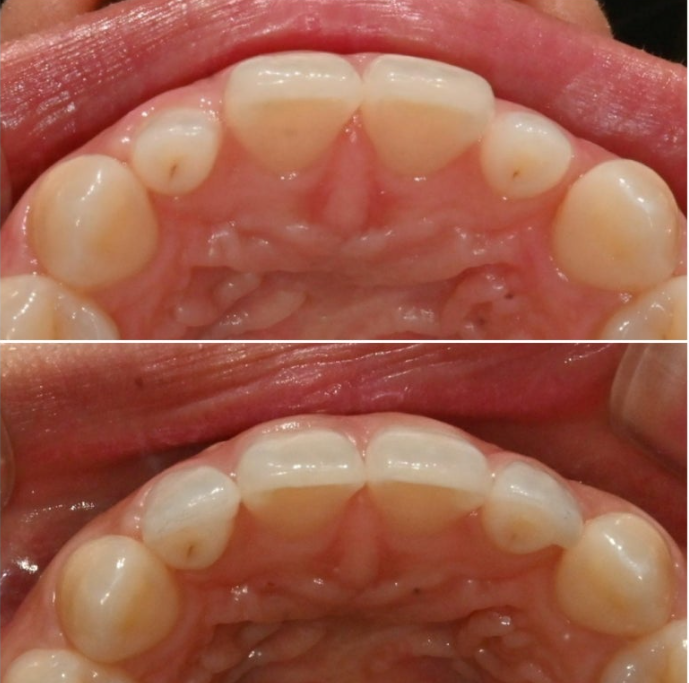

측절치에 왜소치가 있으면 라미네이트로 정상 사이즈 회복을 도모합니다.

물론 왜소치의 정도에 따라 다르고 왜소치이긴 하지만 아래와 교합상 문제가 없거나 작은 정도가 경미하면 라미네이트 없이 교정만으로 해결하기도 합니다.

어쨌든 환자분은 치열이나 교합은 완벽하여 별도의 교정치료는 필요가 없는 상태입니다.

왜소치에 각각 무삭제라미네이트 시술 후 모습입니다.

극강의 얇은 두께로 인해 본래 치아색이 우러나와 생기는 우윳빛 투명감은 젤라미의 특징입니다

깔끔해진 미소가 돋보입니다.